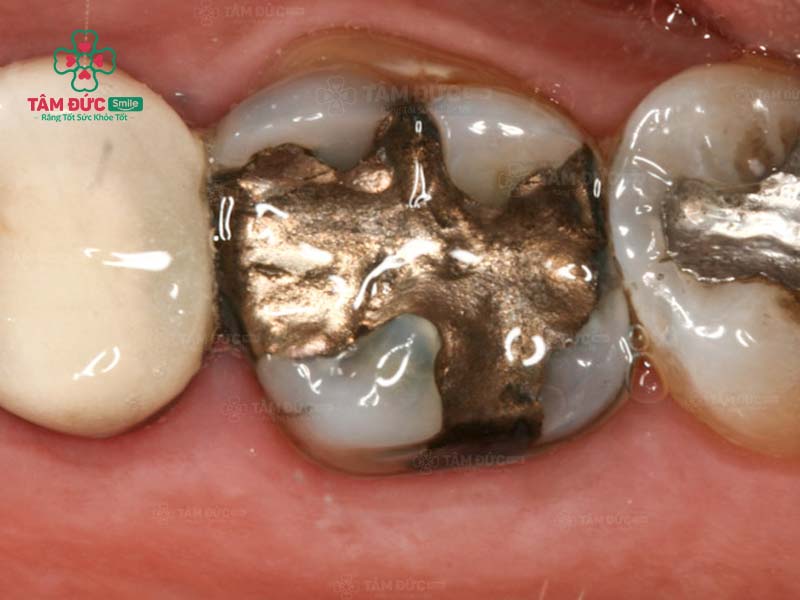

1.4. Thay miếng trám mới

Hiệu quả trám răng không thể duy trì vĩnh viễn. Theo thời gian, miếng trám răng cũ có thể bị bong tróc hoặc rơi ra do tác động từ lực ăn nhai. Trong trường hợp này, bác sĩ sẽ yêu cầu thay miếng trám răng mới.

răng trám cũ và răng trám mới

Quý khách cần trám lại răng khi miếng trám cũ bị bong tróc